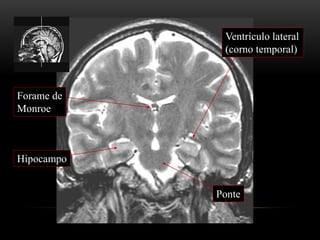

ANATOMIA TOPOGRÁFICA

Plano coronal

III ventrículo

Tálamo

Hipocampo

Ventrículo lateral

(corno temporal)

Ponte

Forame de

Monroe

Mesencéfalo